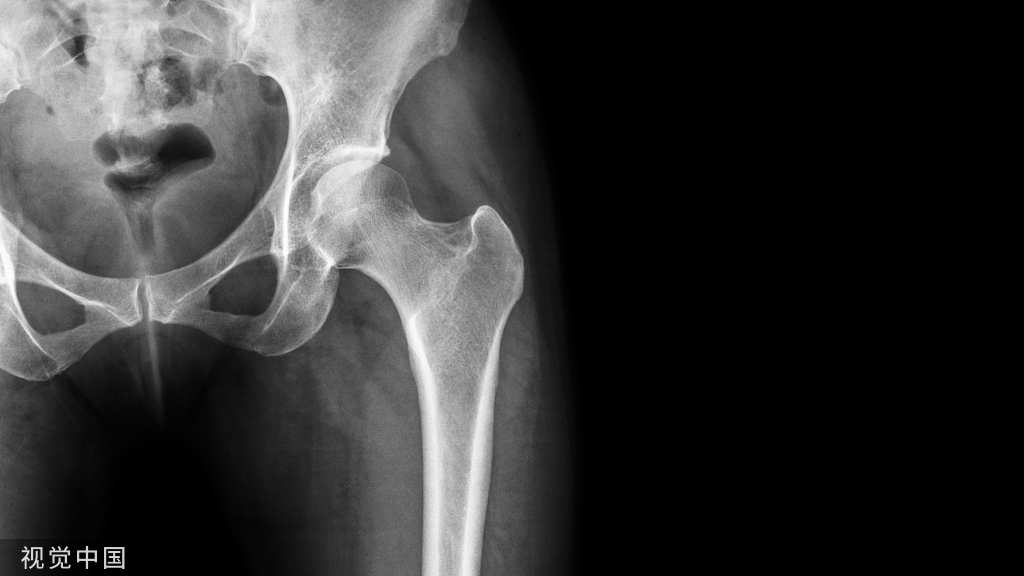

股骨近端正位片

患者牵引床常规仰卧位,患肢牵引下稍内旋,髌骨朝上,健侧肢体外展屈曲固定。透视射线垂直患肢,如下图:

标准正位片示例

正位片图像解剖标记识别1,股骨头;2,股骨颈;3,内侧缘;4,小转子;5,大转子;6,股骨干;7,转子间线。

正位片的作用:判断内外翻畸形、旋转畸形、侧方移位畸形。